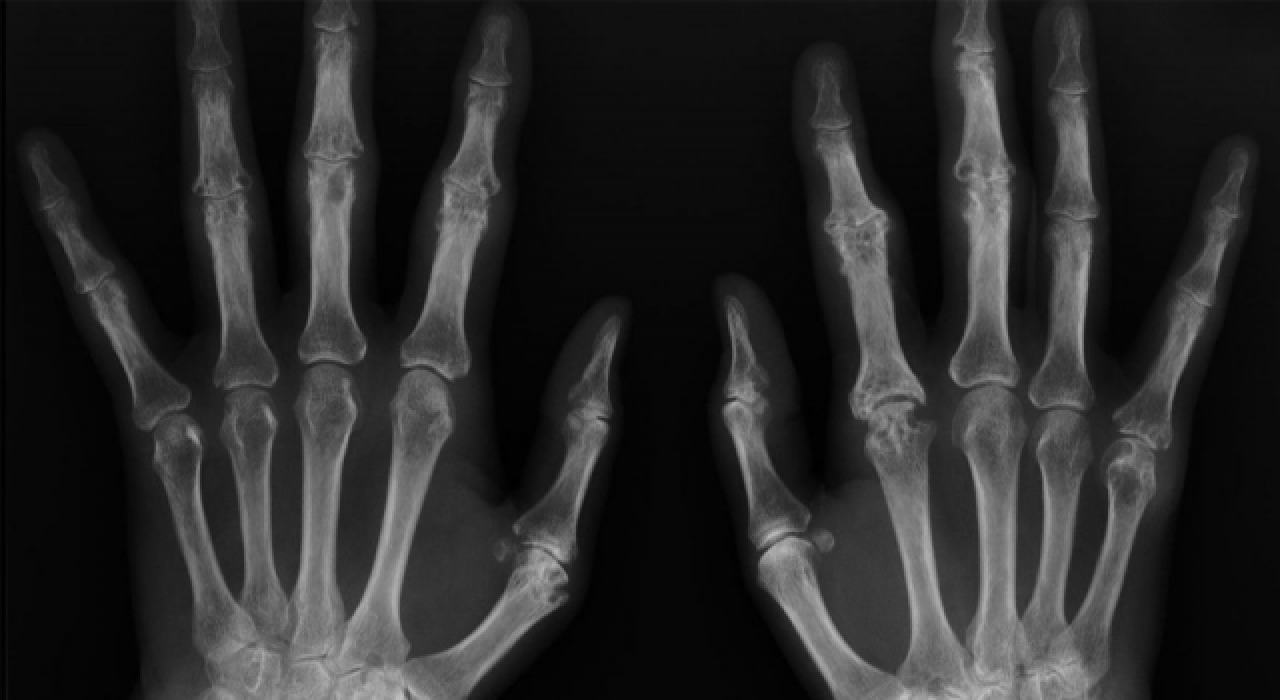

Akademisyenler, kemik yaşını yapay zeka ile bir dakikanın altında sürede tespit edecek sistem geliştirdi.

Siirt Üniversitesi Öğretim Üyesi Doç. Dr. Yılmaz Kaya'nın, iki akademisyenin desteğiyle geliştirdiği, sol el bilek grafisinden kemik yaşı tespitine ilişkin sistemle ilgili makalesi uluslararası dergide yayınlandı.

Çalışmalarıyla, Stanford Üniversitesi bilim insanlarından Prof. Dr. John P. A. Loannidis ve ekibince hazırlanan, Plos Biology Dergisi'nde yayınlanan "Dünyanın en etkili bilim insanları" listesinde 2020 ve 2021 yılında yer alan Siirt Üniversitesi (SİÜ) Mühendislik Fakültesi Bilgisayar Mühendisliği Bölümü Öğretim Üyesi Doç. Dr. Yılmaz Kaya öncülüğünde yapılan sol el bilek grafisinden kemik yaşı tespitine yönelik çalışmalar sonuçlandı.

Kaya'nın SİÜ Teknik Bilimler Meslek Yüksekokulunda Öğretim Görevlisi Cüneyt Özdemir ve Kütahya Sağlık Bilimleri Üniversitesi Evliya Çelebi Eğitim ve Araştırma Hastanesi Radyoloji Uzm. Dr. Mehmet Ali Gedik ile derin öğrenme teknolojisi kullanarak geliştirdiği sistem ile ilgili hazırlanan makale uluslararası kabul gören dergilerden "Traitement du Signal"de yayınlandı.

Akademisyenler yapay zekanın en önemli konularından olan derin öğrenme metotları ile çalışan sistemle ilgili bir de web sitesi oluşturdu.

Herhangi bir gerekçe ile kişinin kemik yaşı tespiti gerektiğinde el bilek görüntüsü sisteme yüklenerek, bir dakikanın altında sürede tespit yapılabilecek.

Bu kapsamda akademisyenler Özdemir ve Gedik ile yaptıkları çalışmada kemik yaşı tahmini için radyologların iş akışını hızlandıracak bir çalışma yürüttüklerini ifade eden Kaya, sol el bilek grafisinden derin öğrenme teknolojisi kullanılarak bilgisayar temelli bir karar destek sistemi geliştirdiklerini belirtti.

Verileri Kütahya'daki 4 hastaneden elde ettiklerini dile getiren Kaya, "Yapay zeka tekniklerini kullanarak el grafilerinden kişinin yaşını tespit etmeye çalıştık. Yaş tespiti çok zahmetli bir şekilde radyologlar tarafından belirleniyor ama bilgisayar sistemiyle çok daha kolay ve hızlı şekilde gerçekleştirebilirsiniz." dedi.

Kaya, el grafisinden kemik yaşı tespitinin daha önce yaklaşık 2 saat sürdüğüne işaret ederek, geliştirdikleri sistemle yaş tespit süresinin saniyelere düştüğünü kaydetti.

"Geliştirdiğimiz sistemle paket program halinde veya web sitesi üzerinden bu çalışmayı saniyelere indirebiliyoruz. Bu, özellikle radyologlar için destekleyici bir program. Bunu Türkiye'deki bütün hastanelere yaymak istiyoruz." diyen Kaya, bunun yanı sıra tüm Türkiye'nin el grafik atlasını da çıkarmaya çalıştıklarını aktardı.

Öğretim görevlisi Cüneyt Özdemir de derin öğrenme yöntemiyle sol el bilek grafisinden kemik yaşı tespitine yönelik çalışmaların 18 yaş altı ve 18 yaş üstü bireylere yönelik iki aşamadan oluştuğunu belirtti.

Özdemir, "Ülkemizde bu işlem için radyologlar genellikle gök atlası dediğimiz sistemden yararlanmakta. Bu yöntemde radyologlar bakış açılarına göre farklı sonuçlar da elde edebiliyorlar. Bu çalışmayla bu işlemi otomatikleştiren, radyologlar için bir karar destek sistemi geliştirdik. Bu sistem uzmanların iş akış sürecini hızlandırıp, kolaylaştıracak." diye konuştu.

18 yaş üstü bireylerin kemik yaşının tespitine yönelik de çalışma yaptıklarını aktaran Özdemir, "18 yaş üstü ile ilgili çalışmalar maalesef ülkemizde ve dünyada az. 18 yaş üstü kemik yaşı tespiti için yüz ve dişlerle ilgili yapılan çalışmalar var. Biz ilk defa el bilek grafisinden 18 yaş üstü kemik yaşının tespitine dönük de bir çalışma yaptık. Bu yöntemle başarılı bir sonuç elde ettik. Bu, literatürde derin öğrenme yöntemiyle 18 yaş üstü kişilerin kemik yaşı tespitine dönük yapılan ilk çalışmalardan biri olma özelliğini taşıyor." ifadelerini kullandı.